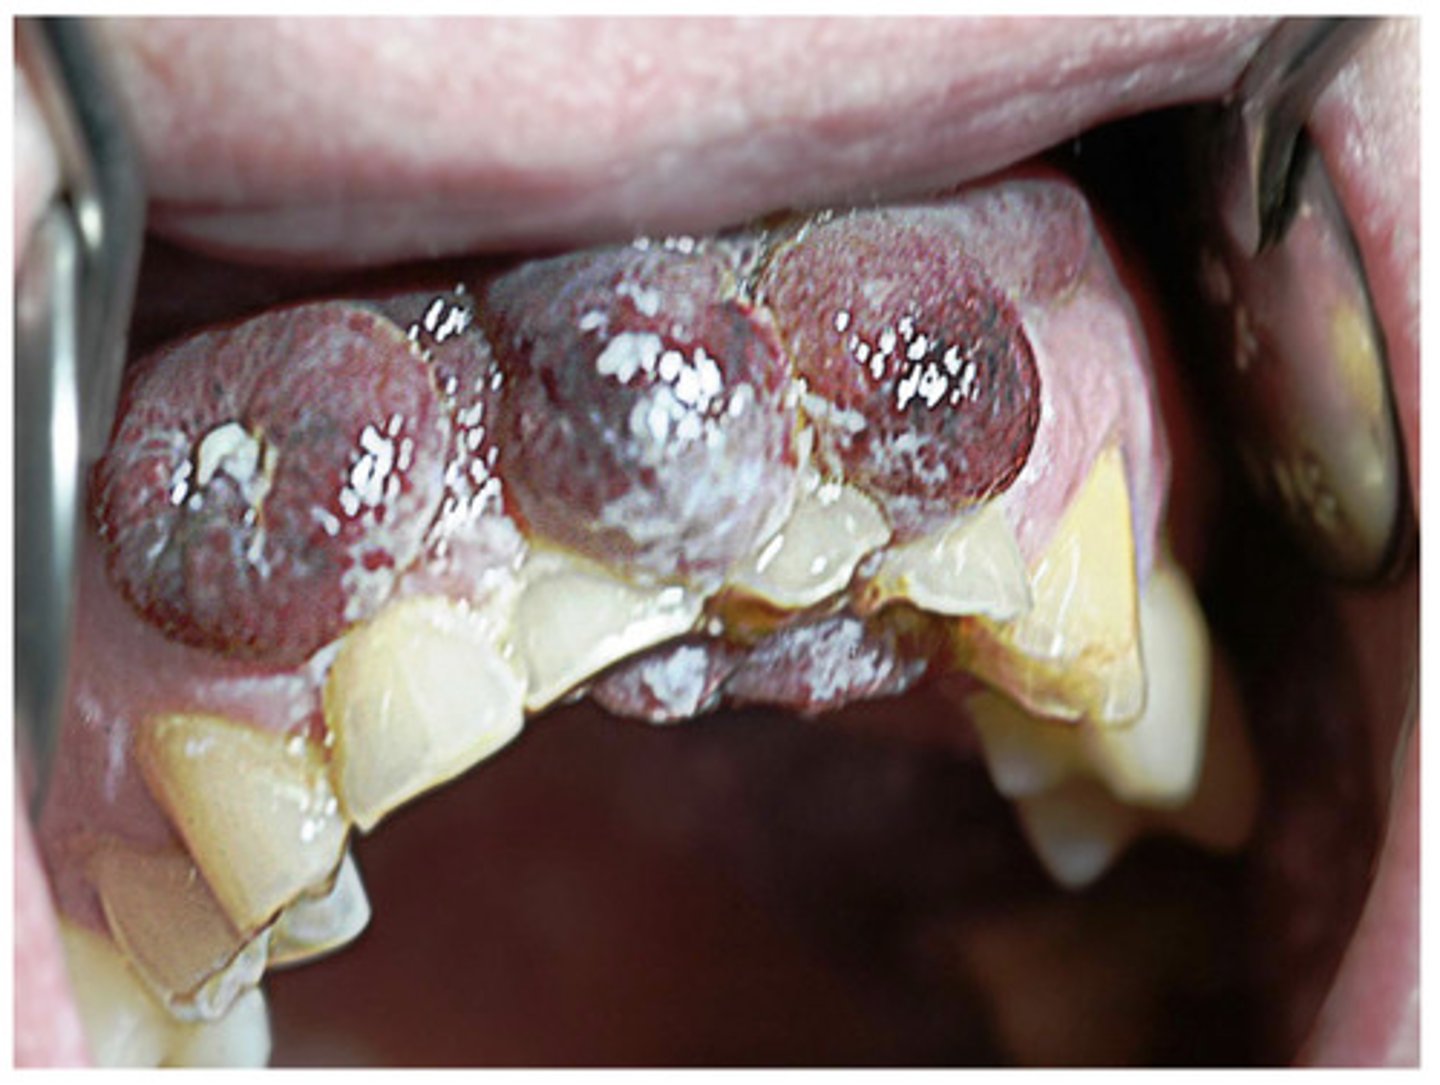

Drug induced gingival hyperplasia

What is this?